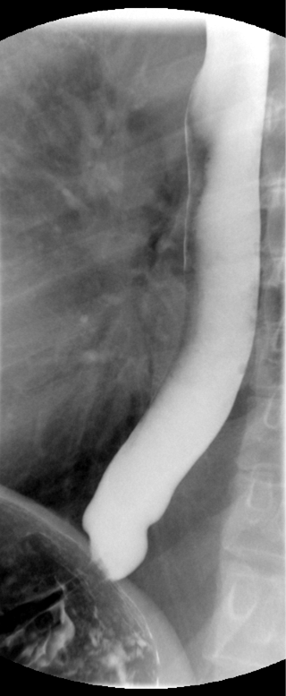

- Take the fluoroscope off rapid sequence.

- With the patient in the lateral position, obtain a spot film of the pharynx and cervical esophagus while they phonate the letter "e"

(key image 2).

- Repeat steps 4-7 with the patient in the AP position

(key image 3)

(key image 4).

- Cervical images are obtained in the lateral and AP projections as the patient swallows thick barium.

- Cervical image are obtained using rapid sequence fluoroscopic spot films at a rate of 4 frames per second.